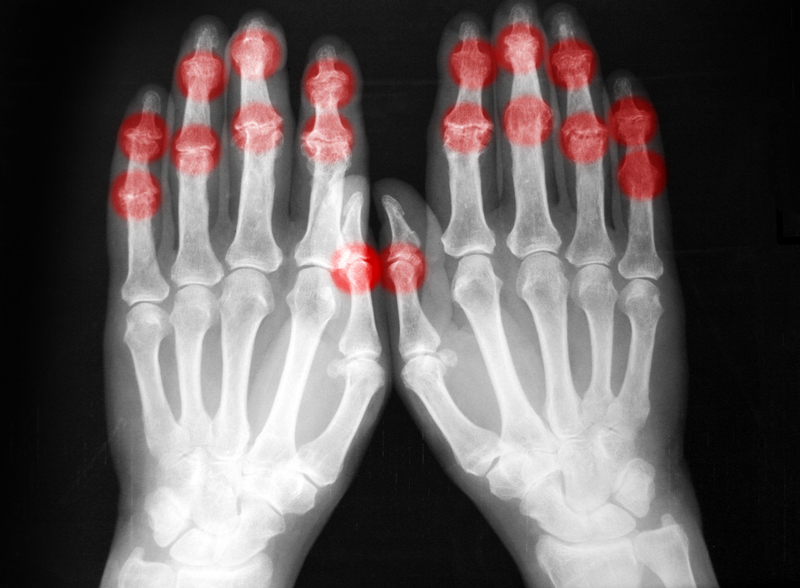

Jayeoba, speaking on the theme “Radiography Practice in the 21st Century: Challenges and Opportunities,” said the complexity of radiography had led many institutions to establish full faculties rather than departments for the discipline.

Highlighting major challenges in the sector, he listed the “rising demand for imaging procedures, increased volume of investigations, growing complexity of cases and a severe shortage of trained professionals.”

He cited available records showing that Nigeria had 183 CT machines in 2018, with Lagos State having 33, Rivers 13, Oyo 11, Anambra 10, Ogun 8 and Kano 8; while the country had only 58 MRI machines as of 2016.

Jayeoba outlined opportunities in general radiography, radiotherapy, nuclear medicine, industrial radiography, magnetic resonance imaging and computerised tomography, urging graduands to remain open to continuous learning.